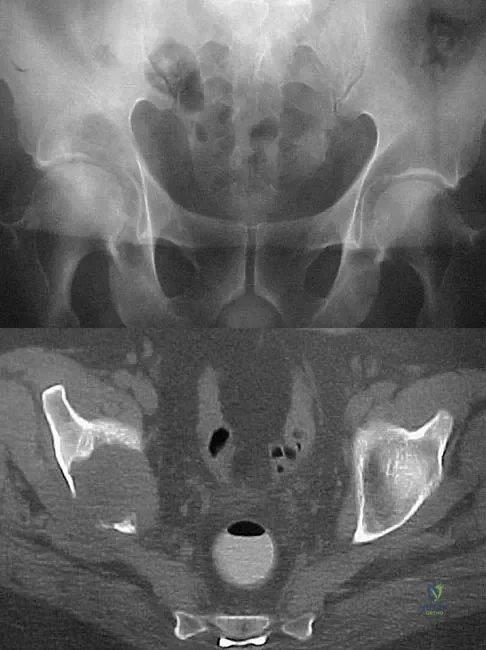

A 50-year-old man with metastatic renal cell carcinoma has right hip pain. A radiograph and CT scan are shown in Figures 48a and 48b. The first step in management should consist of

Explanation